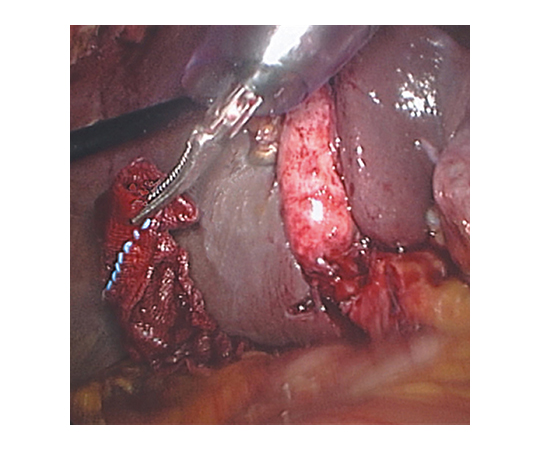

トロックス Cタイプ 30mm×150mm 1ply 5枚入×20袋

●ストレスのない操作性を実現した、X線造影糸入り鏡視下手術用滅菌ガーゼです。 ●トロッカーからワンプッシュで挿入することができます。 ●血管周囲及び神経線維組織の剥離をする際に有効です。 ●ガーゼの積層により十分な血液・体液などの吸収が得られます。 ●対角線上に入れたX線造影糸を目安に角部を鉗子で把持して引くことにより、ガーゼが直線化し、吸収した血液や体液をトロッカー先端で絞ることなく取り出すことができます。

●種類:Cタイプ ●サイズ:30mm×150mm 1ply ●入数:5枚入(20袋) ●材質:[ガーゼ]綿 100%[X線造影糸](固定材)ポリプロピレン、ポリエステル(造影剤)硫酸バリウム(着色剤)深海青グレード02